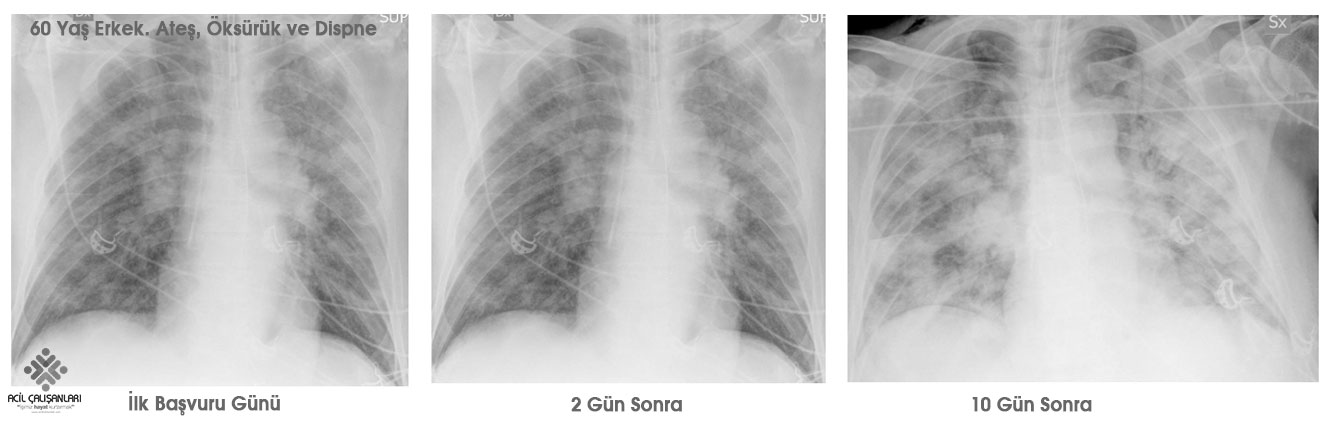

Covid 19 Radyolojik Goruntuleme Acil Calisanlari